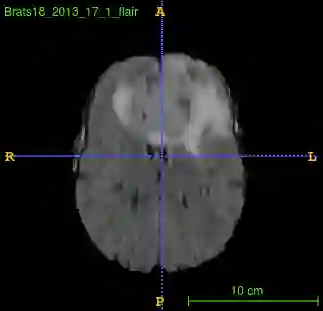

Segmentation of brain tumor from magnetic resonance imaging (MRI) is a vital process to improve diagnosis, treatment planning and to study the difference between subjects with tumor and healthy subjects. In this paper, we exploit a convolutional neural network (CNN) with hypercolumn technique to segment tumor from healthy brain tissue. Hypercolumn is the concatenation of a set of vectors which form by extracting convolutional features from multiple layers. Proposed model integrates batch normalization (BN) approach with hypercolumn. BN layers help to alleviate the internal covariate shift during stochastic gradient descent (SGD) training by zero-mean and unit variance of each mini-batch. Survival Prediction is done by first extracting features(Geometric, Fractal, and Histogram) from the segmented brain tumor data. Then, the number of days of overall survival is predicted by implementing regression on the extracted features using an artificial neural network (ANN). Our model achieves a mean dice score of 89.78%, 82.53% and 76.54% for the whole tumor, tumor core and enhancing tumor respectively in segmentation task and 67.90% in overall survival prediction task with the validation set of BraTS 2018 challenge. It obtains a mean dice accuracy of 87.315%, 77.04% and 70.22% for the whole tumor, tumor core and enhancing tumor respectively in the segmentation task and a 46.80% in overall survival prediction task in the BraTS 2018 test data set.